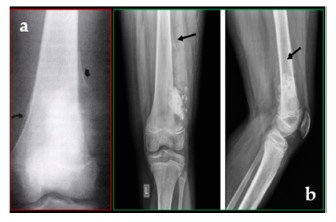

Radiografía de osteosarcoma.

El osteosarcoma y el sarcoma de Ewing son las dos neoplasias óseas malignas más prevalentes en la infancia y su diagnóstico temprano es esencial para mejorar el pronóstico de los pacientes. Según el estudio, "el osteosarcoma es el tumor óseo maligno más común en niños, con una frecuencia de 4,4 casos por millón de habitantes, seguido por el sarcoma de Ewing, cuya incidencia es de 2,5 a 3 casos por millón de habitantes". Estas neoplasias presentan una alta agresividad y, en muchos casos, se detectan cuando ya han desarrollado metástasis, lo que complica su curación.

Desde una perspectiva histológica, el estudio señala que "el osteosarcoma es un tumor osteogénico de alto grado caracterizado por la producción de matriz osteoide por células mesenquimales malignas, mientras que el sarcoma de Ewing es una neoplasia de células pequeñas y redondas, con translocaciones cromosómicas recurrentes", explica el profesor Ortega Ruiz.

El diagnóstico de estas neoplasias requiere un enfoque integral que combine técnicas radiológicas avanzadas y análisis histopatológicos. En este sentido, la investigación destaca que "el estándar de oro para el diagnóstico incluye el examen de rayos X y la resonancia magnética, que brinda una evaluación precisa de la extensión del tumor al canal medular y los tejidos blandos circundantes". Además, la tomografía por emisión de positones (PET) con fluorodesoxiglucosa (FDG) permite evaluar la agresividad del tumor y detectar metástasis a distancia.